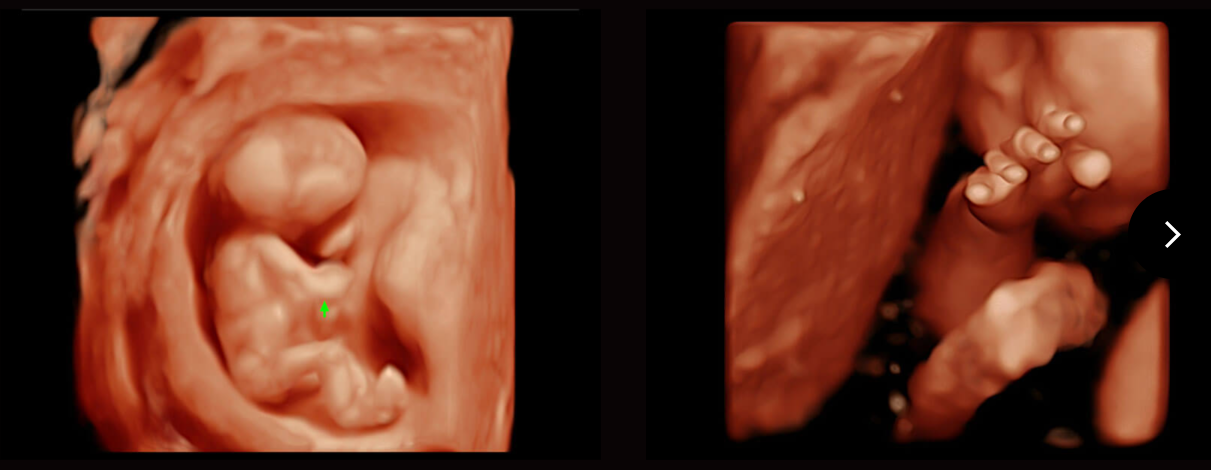

S-Fetus

Tự động phát hiện và đo 16 thông số thai nhi bằng trí tuệ nhân tạo AI trong quy trình siêu âm sản khoa.

Tự động thu thập mặt phẳng tiêu chuẩn (có sẵn trên BPD/AC/HC/FL).

Sinh trắc học và báo cáo tự động.

Đã xác minh hơn 10000 trường hợp với độ chính xác 98%.

Auto Face

Tự động nhận diện khuôn mặt

Tự động tối ưu hóa khuôn mặt thai nhi 3D

Tự động loại bỏ tình trạng tắc nghẽn ở phía trước khuôn mặt thai nhi

Nhận dạng chính xác cấu trúc giải phẫu khuôn mặt thai nhi